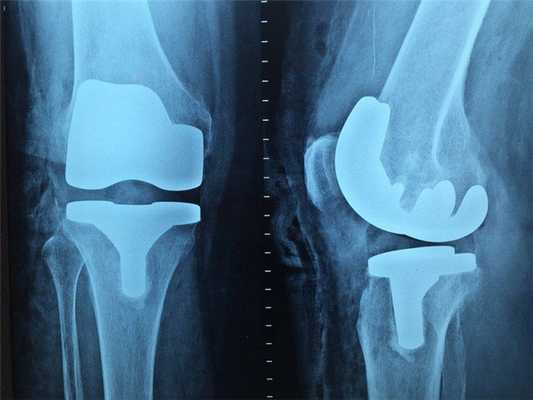

Патология

Они могут развиваться в любом месте скелета, однако самая типичная локализация — метафизы длинных костей, составляющих коленный сустав. Диафизарное расположение — не редкость. У молодых пациентов преимущественно поражаются трубчатые, у взрослых — одинаково часто трубчатые и плоские, у лиц старше 50 лет — в основном плоские кости.

Локализация:

- Бедро 40% (дистальная часть).

- Берцовая кость 16% (проксимальная часть)

- Плечевая кость 15%

Радиологические находки

Рентгенологически условно различают:

2) остеолитическую и

3) смешанную разновидности остеосаркомы.

При остеобластическом типе превалирует склерозирование патологического очага, не распространяющееся через ростковую зону. Наблюдается раннее разрушение кортикального слоя, образование периостального «козырька», спикул, мягкотканного компонента, в структуре которого обнаруживаются участки патологического костеобразования. Примерно в каждом четвертом случае возникают т. н. «прыгающие» метастазы — очаги остеобластического роста в других отделах той же кости.

Остеолитические формы отличаются преобладанием деструкции без склеротической реакции. На ранних этапах единственным проявлением саркомы может служить нежная периостальная реакция с подлежащим участком разрежения костной структуры. Деструктивный очаг (центральный или эксцентричный) быстро распространяется вдоль и поперек кости в виде сливающихся мелких очагов («изъеденность молью»), разрушается кортикальный слой. Наряду с многослойной линейной реакцией, периостальным «козырьком» можно наблюдать спикулы различной длины и толщины, исходящие как бы из одного центра (в отличие от костномозговых сарком). Примерно в 20 % случаев, в основном у детей, наблюдается патологический перелом.